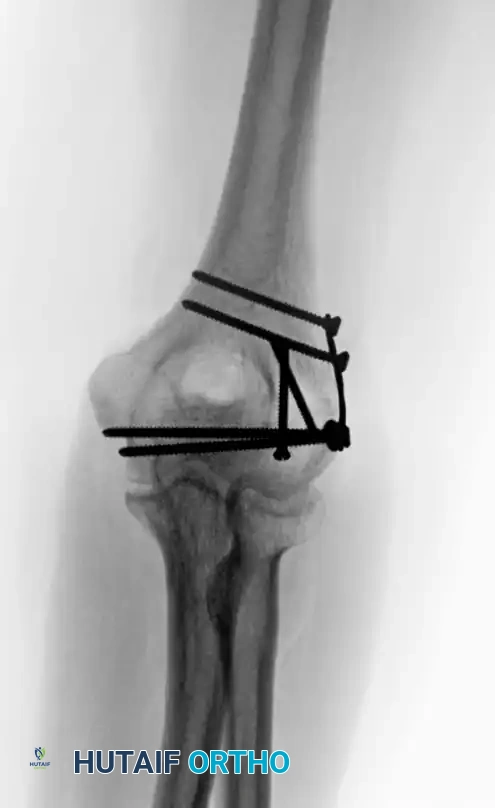

Intraoperative view of plate application through a triceps-reflecting approach, preserving the extensor mechanism.

Radiographic confirmation of bicolumnar fixation achieved via a triceps-reflecting exposure.

These approaches are particularly advantageous when total elbow arthroplasty (TEA) is considered as a backup option, or in patients with severe osteopenia where osteotomy healing is questionable.